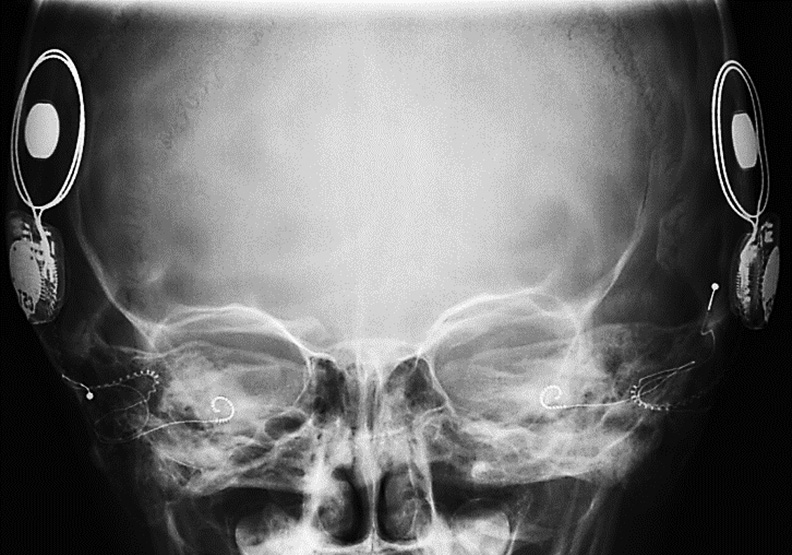

Кохлеарная имплантация – это операция по установке специального электронного устройства («кохлеарного импланта»), которое улавливает звуки и преобразует их в электрические импульсы, направляемые во внутреннее ухо, что дает возможность слышать. Стандартная операция по установке кохлеарного импланта длится около 1,5 часа, в ходе которой устройство помещается в заушной зоне, а электроды вводятся в улитку. После кохлеарной имплантации при подключении речевого процессора и настройки необходимо научить пациента воспринимать, различать звуки и использовать эти знания для развития речи. (рис. 23).

Рис. 23. КТ-рентгенограмма пациента после кохлеарной имплантации / Fig. 23. CT-radiograph of a patient after cochlear implantation